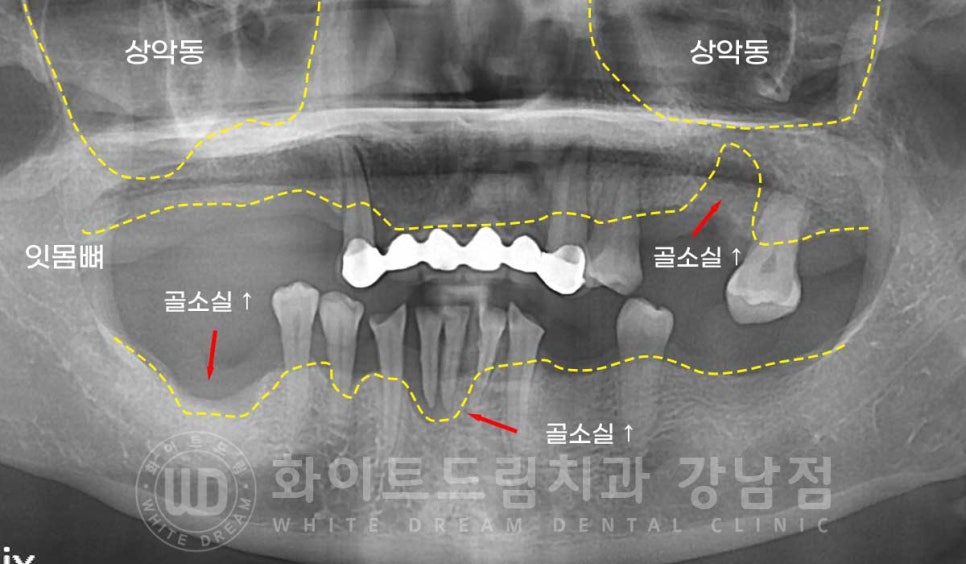

환자분은 현재 남아있는 치아들이 심하게 흔들리는 상태였습니다.

치주염으로 잇몸뼈가 많이 녹아내려 잇몸뼈가 치아를 잡아주는 면적이 크게 줄었기 때문입니다.

환자분의 경우 치아를 상실한지 시간이 오래되기도 했고

염증으로 인해 치아를 발치했던 상태여서 잇몸뼈 소실이 큰 부위가 있었기에

이 부분은 임플란트 식립 시 뼈이식을 동반하여 모자란 뼈를 보강해 주기로 했답니다.

그리고 어금니의 상실로 인해 치아의 교합면이 심하게 낮아진 상태여서

보철 세팅 시 낮아진 교합 높이(수직 고경)을 회복할 수 있도록 치료 계획을 세우게 되었습니다.

▲ 어금니 상실로 인해 낮아진 수직 고경(상/하악 어금니가 사라지면서 치아의 씹는 높이가 상실된 상태)